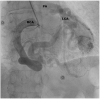

Case summary: We present a case of a 76-year-old patient with first presentation of ALCAPA. The coronary anomaly was first diagnosed during elective coronary angiography. The case was discussed at the Heart Team meeting and as the patient was asymptomatic, had good coronary collateral circulation, a medical treatment strategy was chosen and the patient was discharged in a good physical condition. During 3 years of follow-up, the patient has experienced no cardiovascular complications.